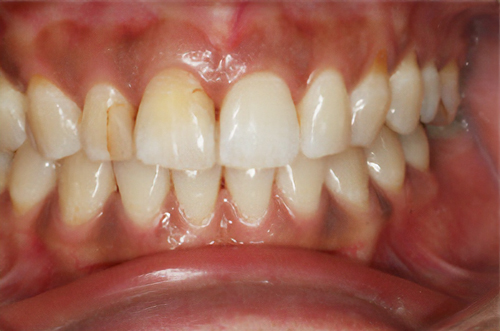

黒ずんだ歯肉の色をお薬で、キレイなピンク色の歯肉にします。

塗り薬の麻酔と薬液だけで10分程度、2回の治療でキレイなピンク色に。-

術前

術後